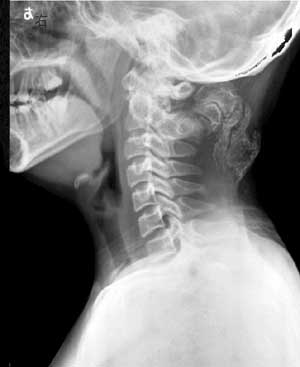

以下是引用向医生在2004-6-27 8:13:44的发言:[br]颈后部巨大肿块,内有多量钙化及骨化影,肿块与枢椎棘突似有薄蒂相连.[br]意见:颈后部肿块考虑以枢椎外生软骨瘤可能性大,其次考虑骨外软骨瘤.

以下是引用曼一拍在2004-6-30 23:46:56的发言:[br]抄书:进行性骨化性肌炎也叫进行性骨化性纤维发育不良。是一种少见的遗传性发育不良(多为常染色体显性遗传),先天性骨异常合并严重进行性的软组织骨化。病因不明,无有效治疗方法。[br]临床可有:耳聋.脱发.智力迟钝.骨骼畸形和关节活动受限。[br]x线表现:1. 软组织骨化:出生一月可有,骨化多自项韧带或胸锁乳突肌开始。进行性,直至20-30岁全身大部分结缔组织和肌肉都发生骨化,脊柱和大关节僵直。2.骨骼异常:主要在手和足的拇,以拇趾短为主,且有先性拇外翻。3.关节改变:长骨干骺异常,关节半脱位等。[br] 故,我支持向医生。